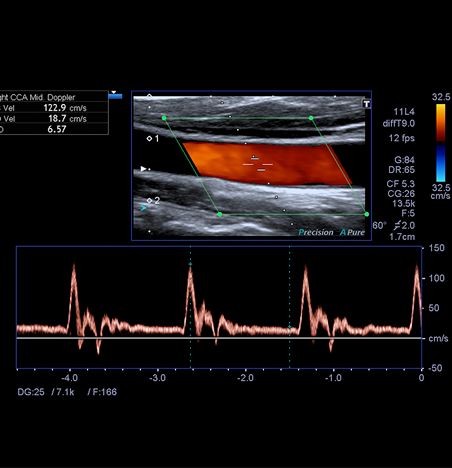

Le doppler est une technique permettant l’analyse des vaisseaux artériels et veineux :

– suspicion de phlébite

– suspicion de sténose des troncs artériels supra aortiques (TSA)

– surveillance de greffon rénal ou hépatique

– écho-doppler des artères rénales

– suivi de cirrhose hépatique

– bilan de varicocèle